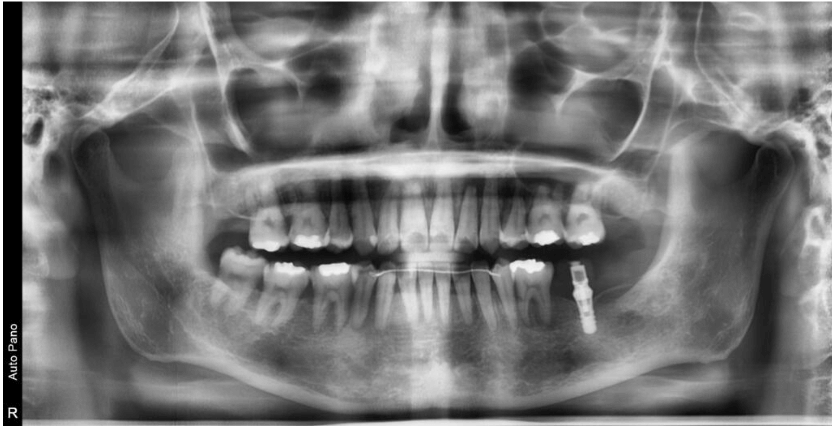

インプラントと矯正治療の融合治療!

| 治療内容 | 上顎右側第一小臼歯、上顎左側第二小臼歯、下顎両側第二臼歯を抜歯しマルチブラケット法にて配列を行った。 上顎歯列の加強固定を目的にアンカースクリューを埋入した。 また下顎左側第二大臼歯は予後不良のため、抜歯を行い、矯正治療終盤にインプラントにて修復を行なっている。 保定装置は上顎Beggリテーナー、下顎はフィックスリテーナーにて保定管理を行っている。 担当医 里 裕太郎 |